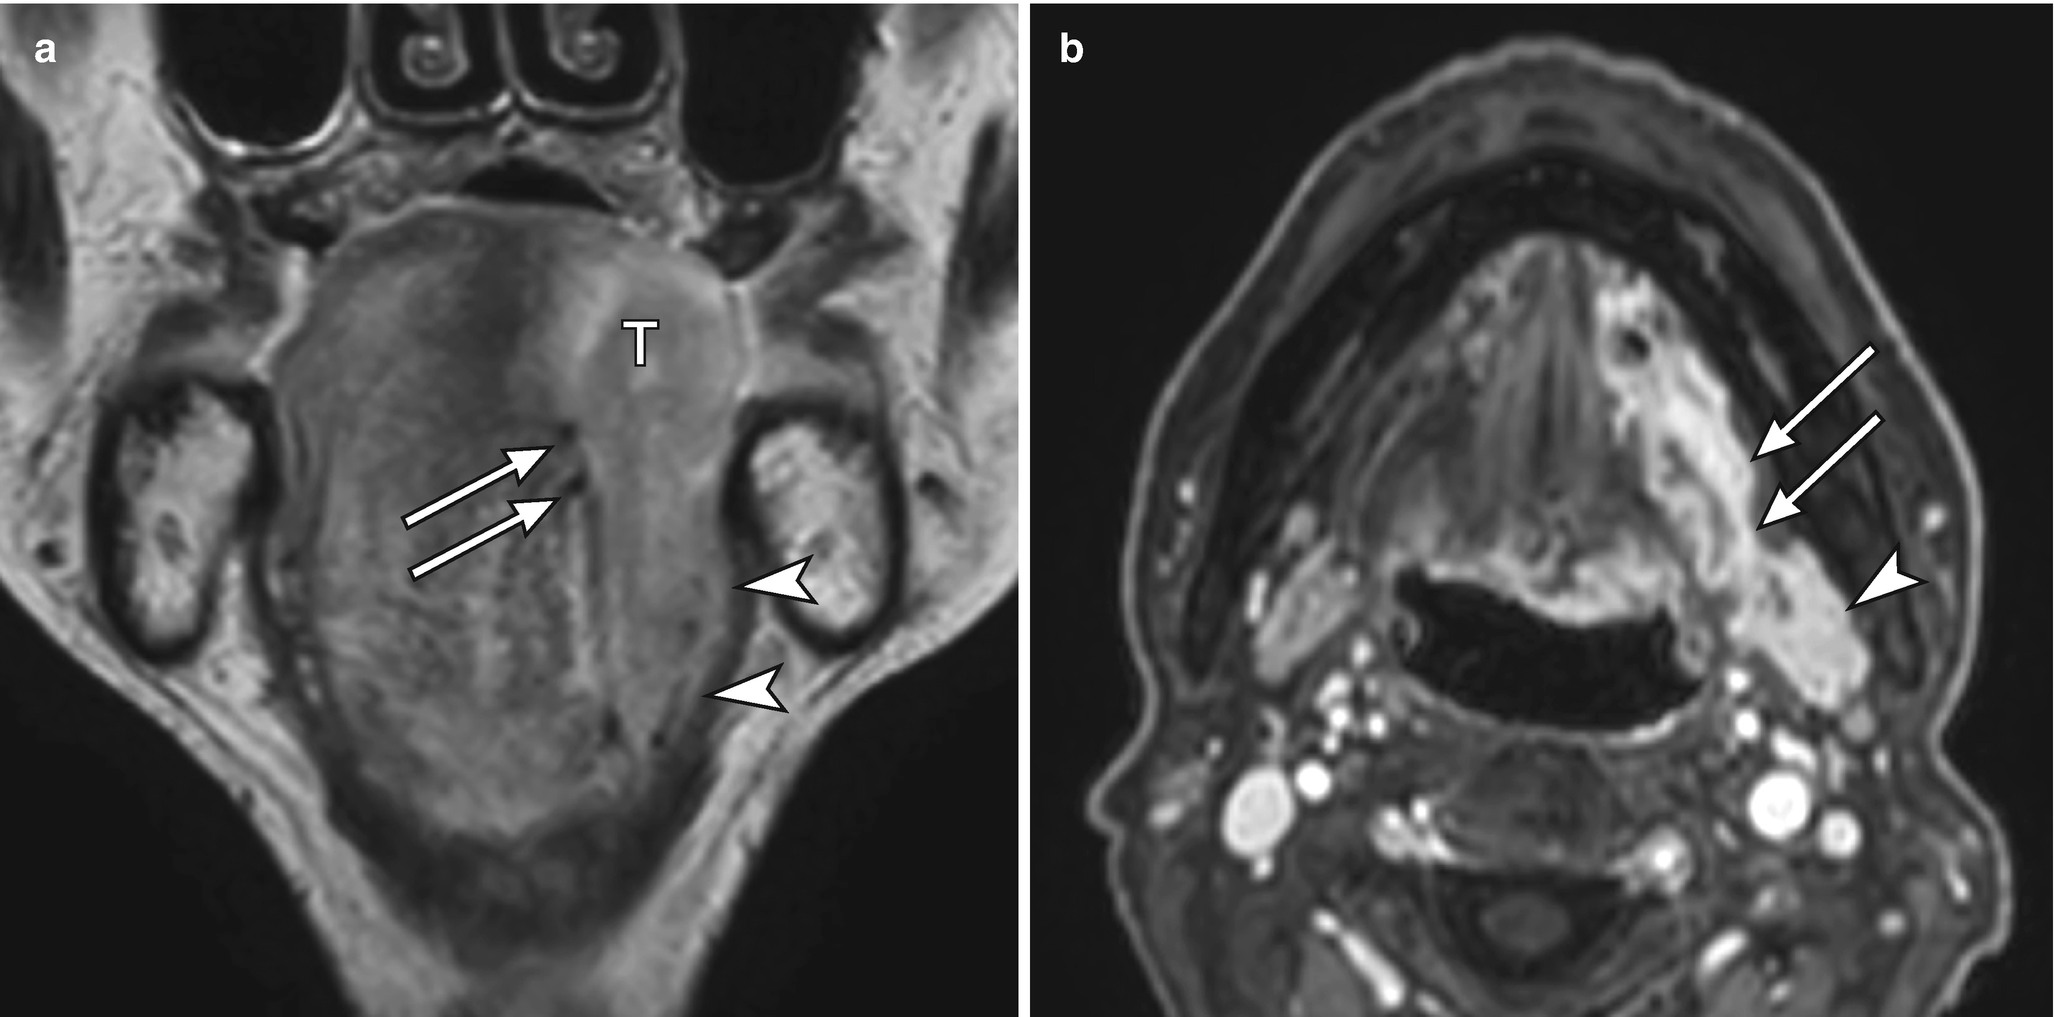

Axial and coronal ct scans demonstrating communication of infratemporal fossa with figure 17: The gingivobuccal complex is a broad term and encompasses the following figures 10b, c: Probe the gingival sulcus to determine the biologic width. The depth of the sulcus (latin for groove) is bounded by two entities: